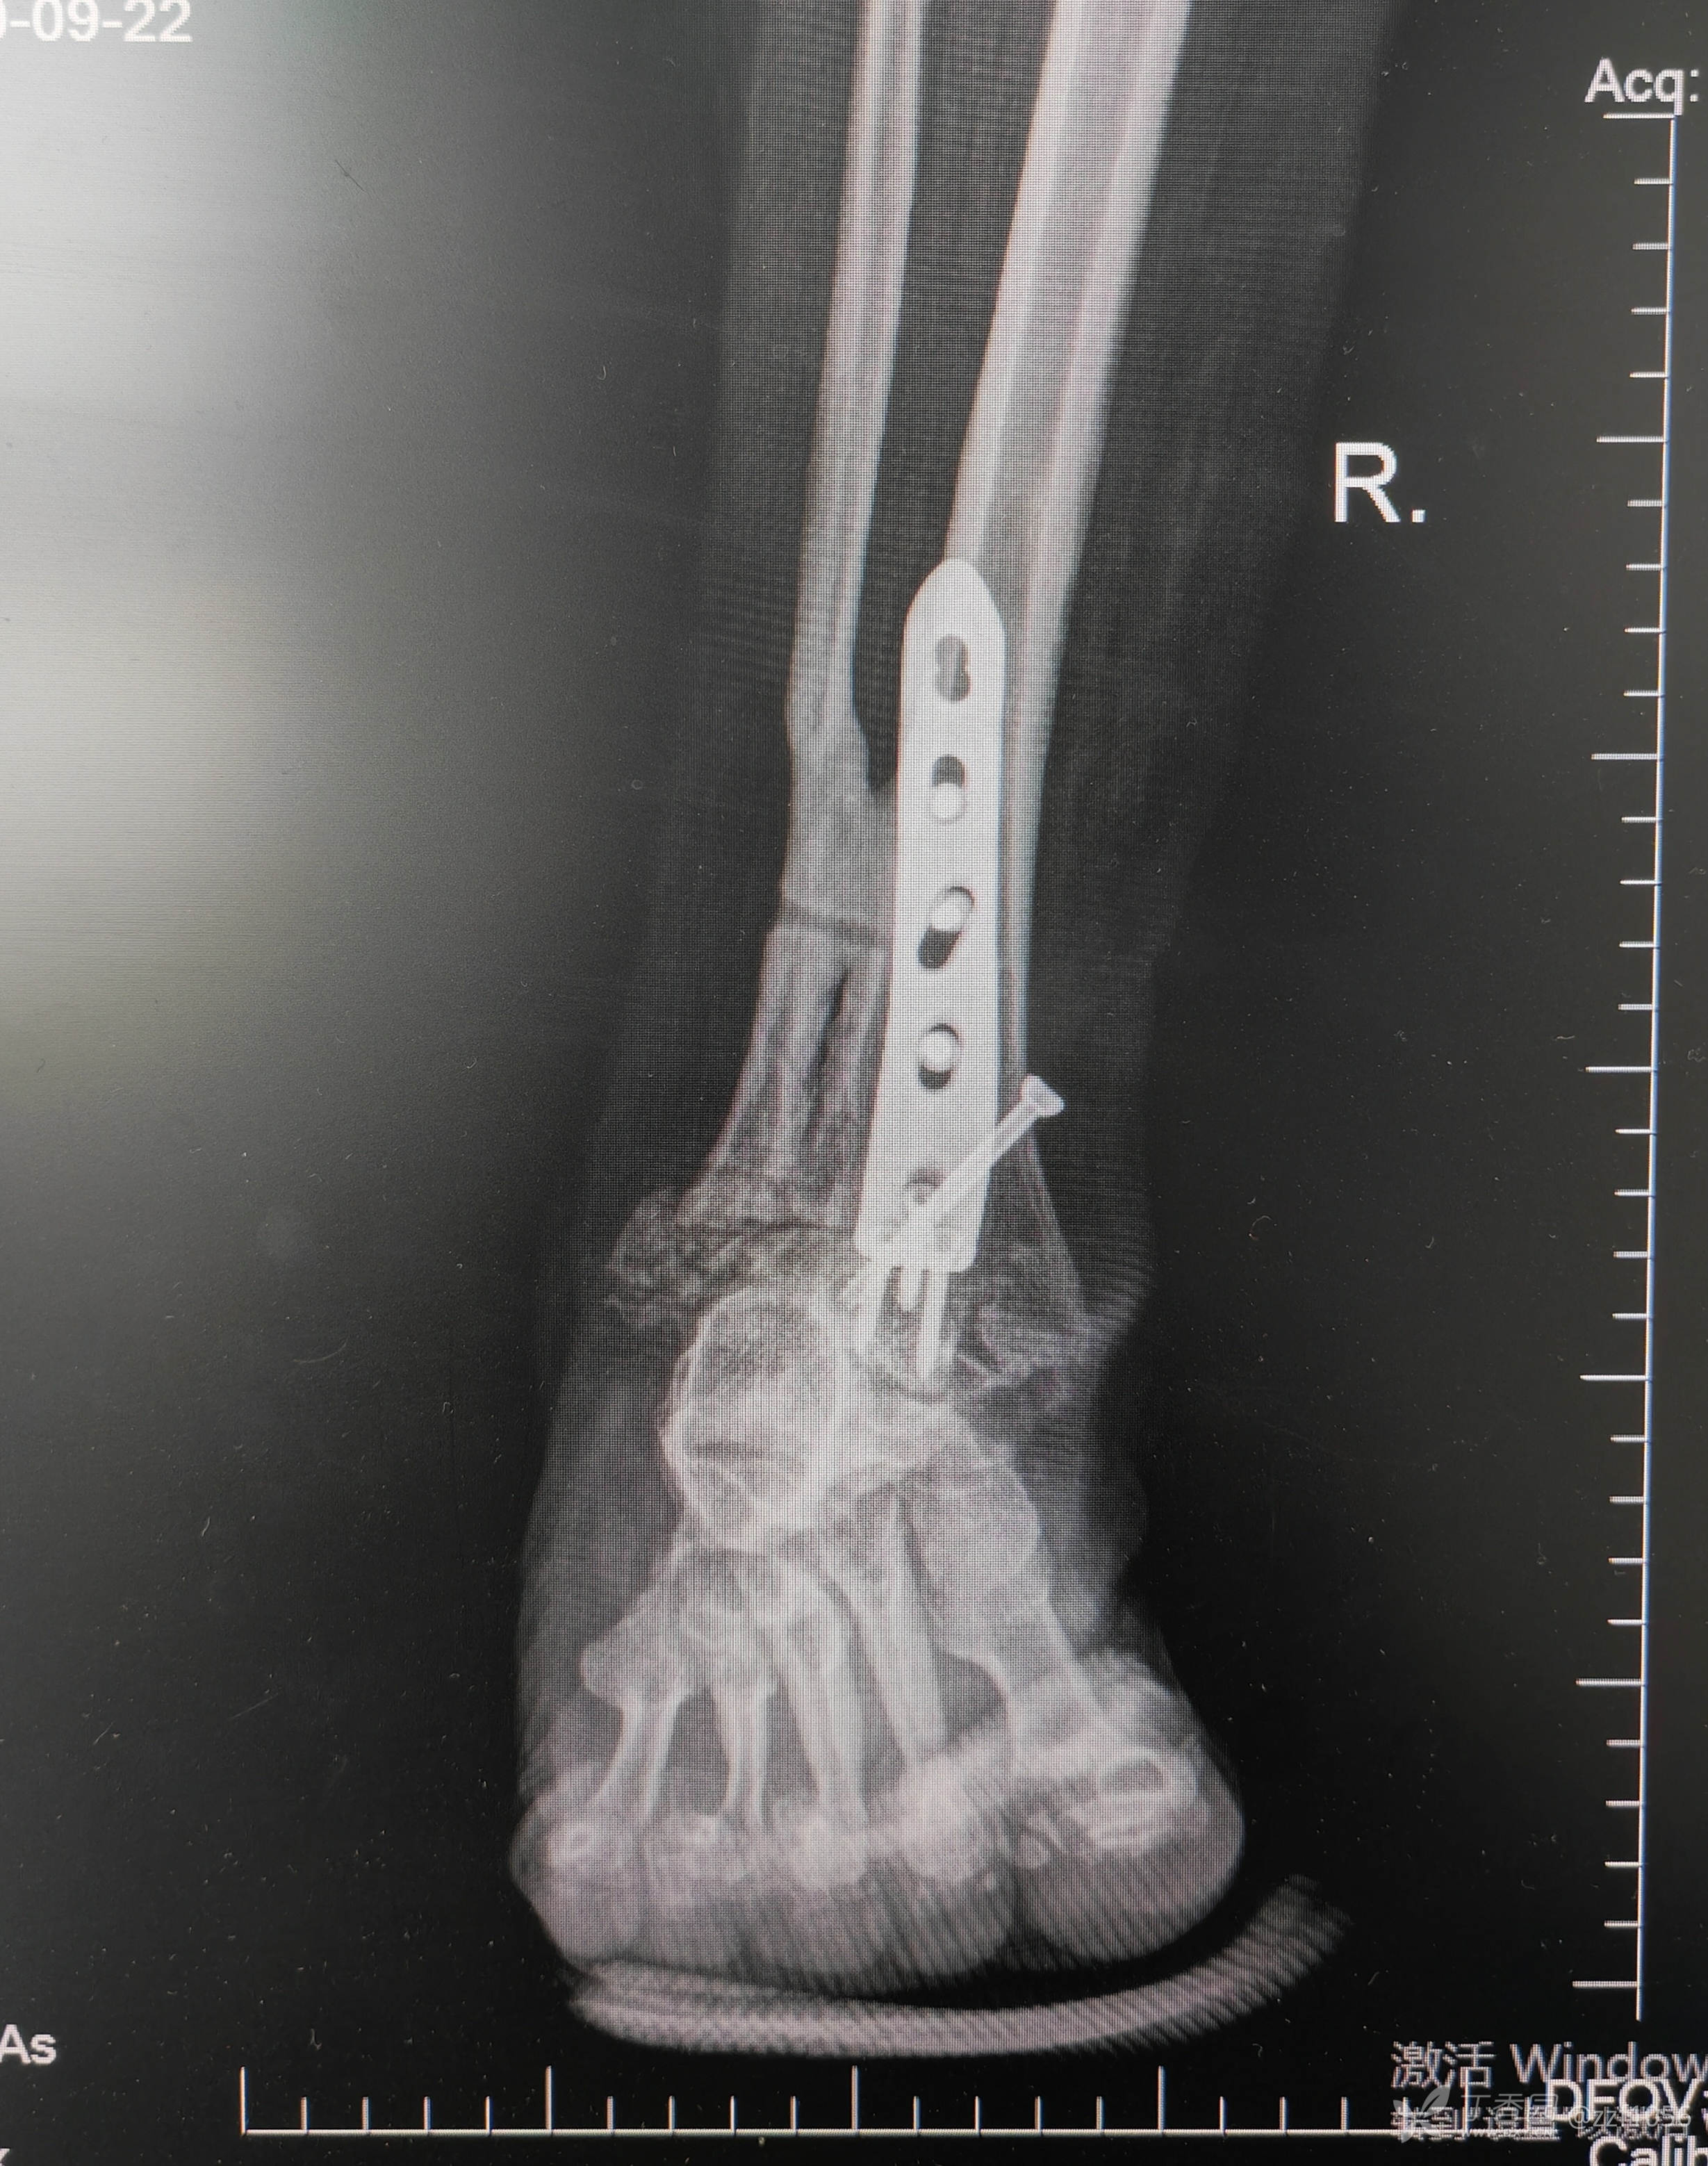

入院诊断:右踝关节骨折术后畸形融合,内固定存留

从骨折畸形愈合形态应该能推测当时接近于劈木机损伤,旋前外旋四度骨折。

正位片力线